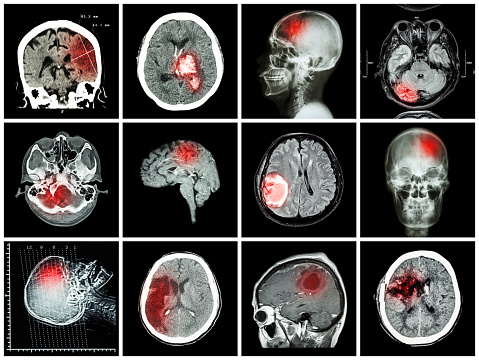

Complex partial seizures: Causes, symptoms, diagnosis, and treatment

By definition, complex partial seizures only affect specific areas of the brain rather than the entire brain simultaneously. Like other types of seizures, they’re characterized by various electrical surges of energy that take place in different portions of the brain. This sensation can be caused by any number of mitigating factors, which will be discussed ...click here to read more